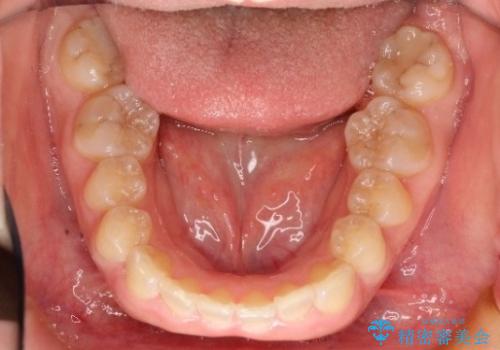

初診時の歯並びの状態としては、上の前歯が下に対して前に飛び出た上顎前突という状態で、前歯は大きく前に飛び出した状態により患者様も口の閉じづらさを感じているとのことでした。また上顎に軽度の叢生(ガタガタ)がありました。

抜歯は行わず上顎の奥のスペースを利用して歯をスライドする方法の他に歯列弓の拡大やディスキング(歯と歯の間の隙間を作る処置)を行い叢生を改善しました。